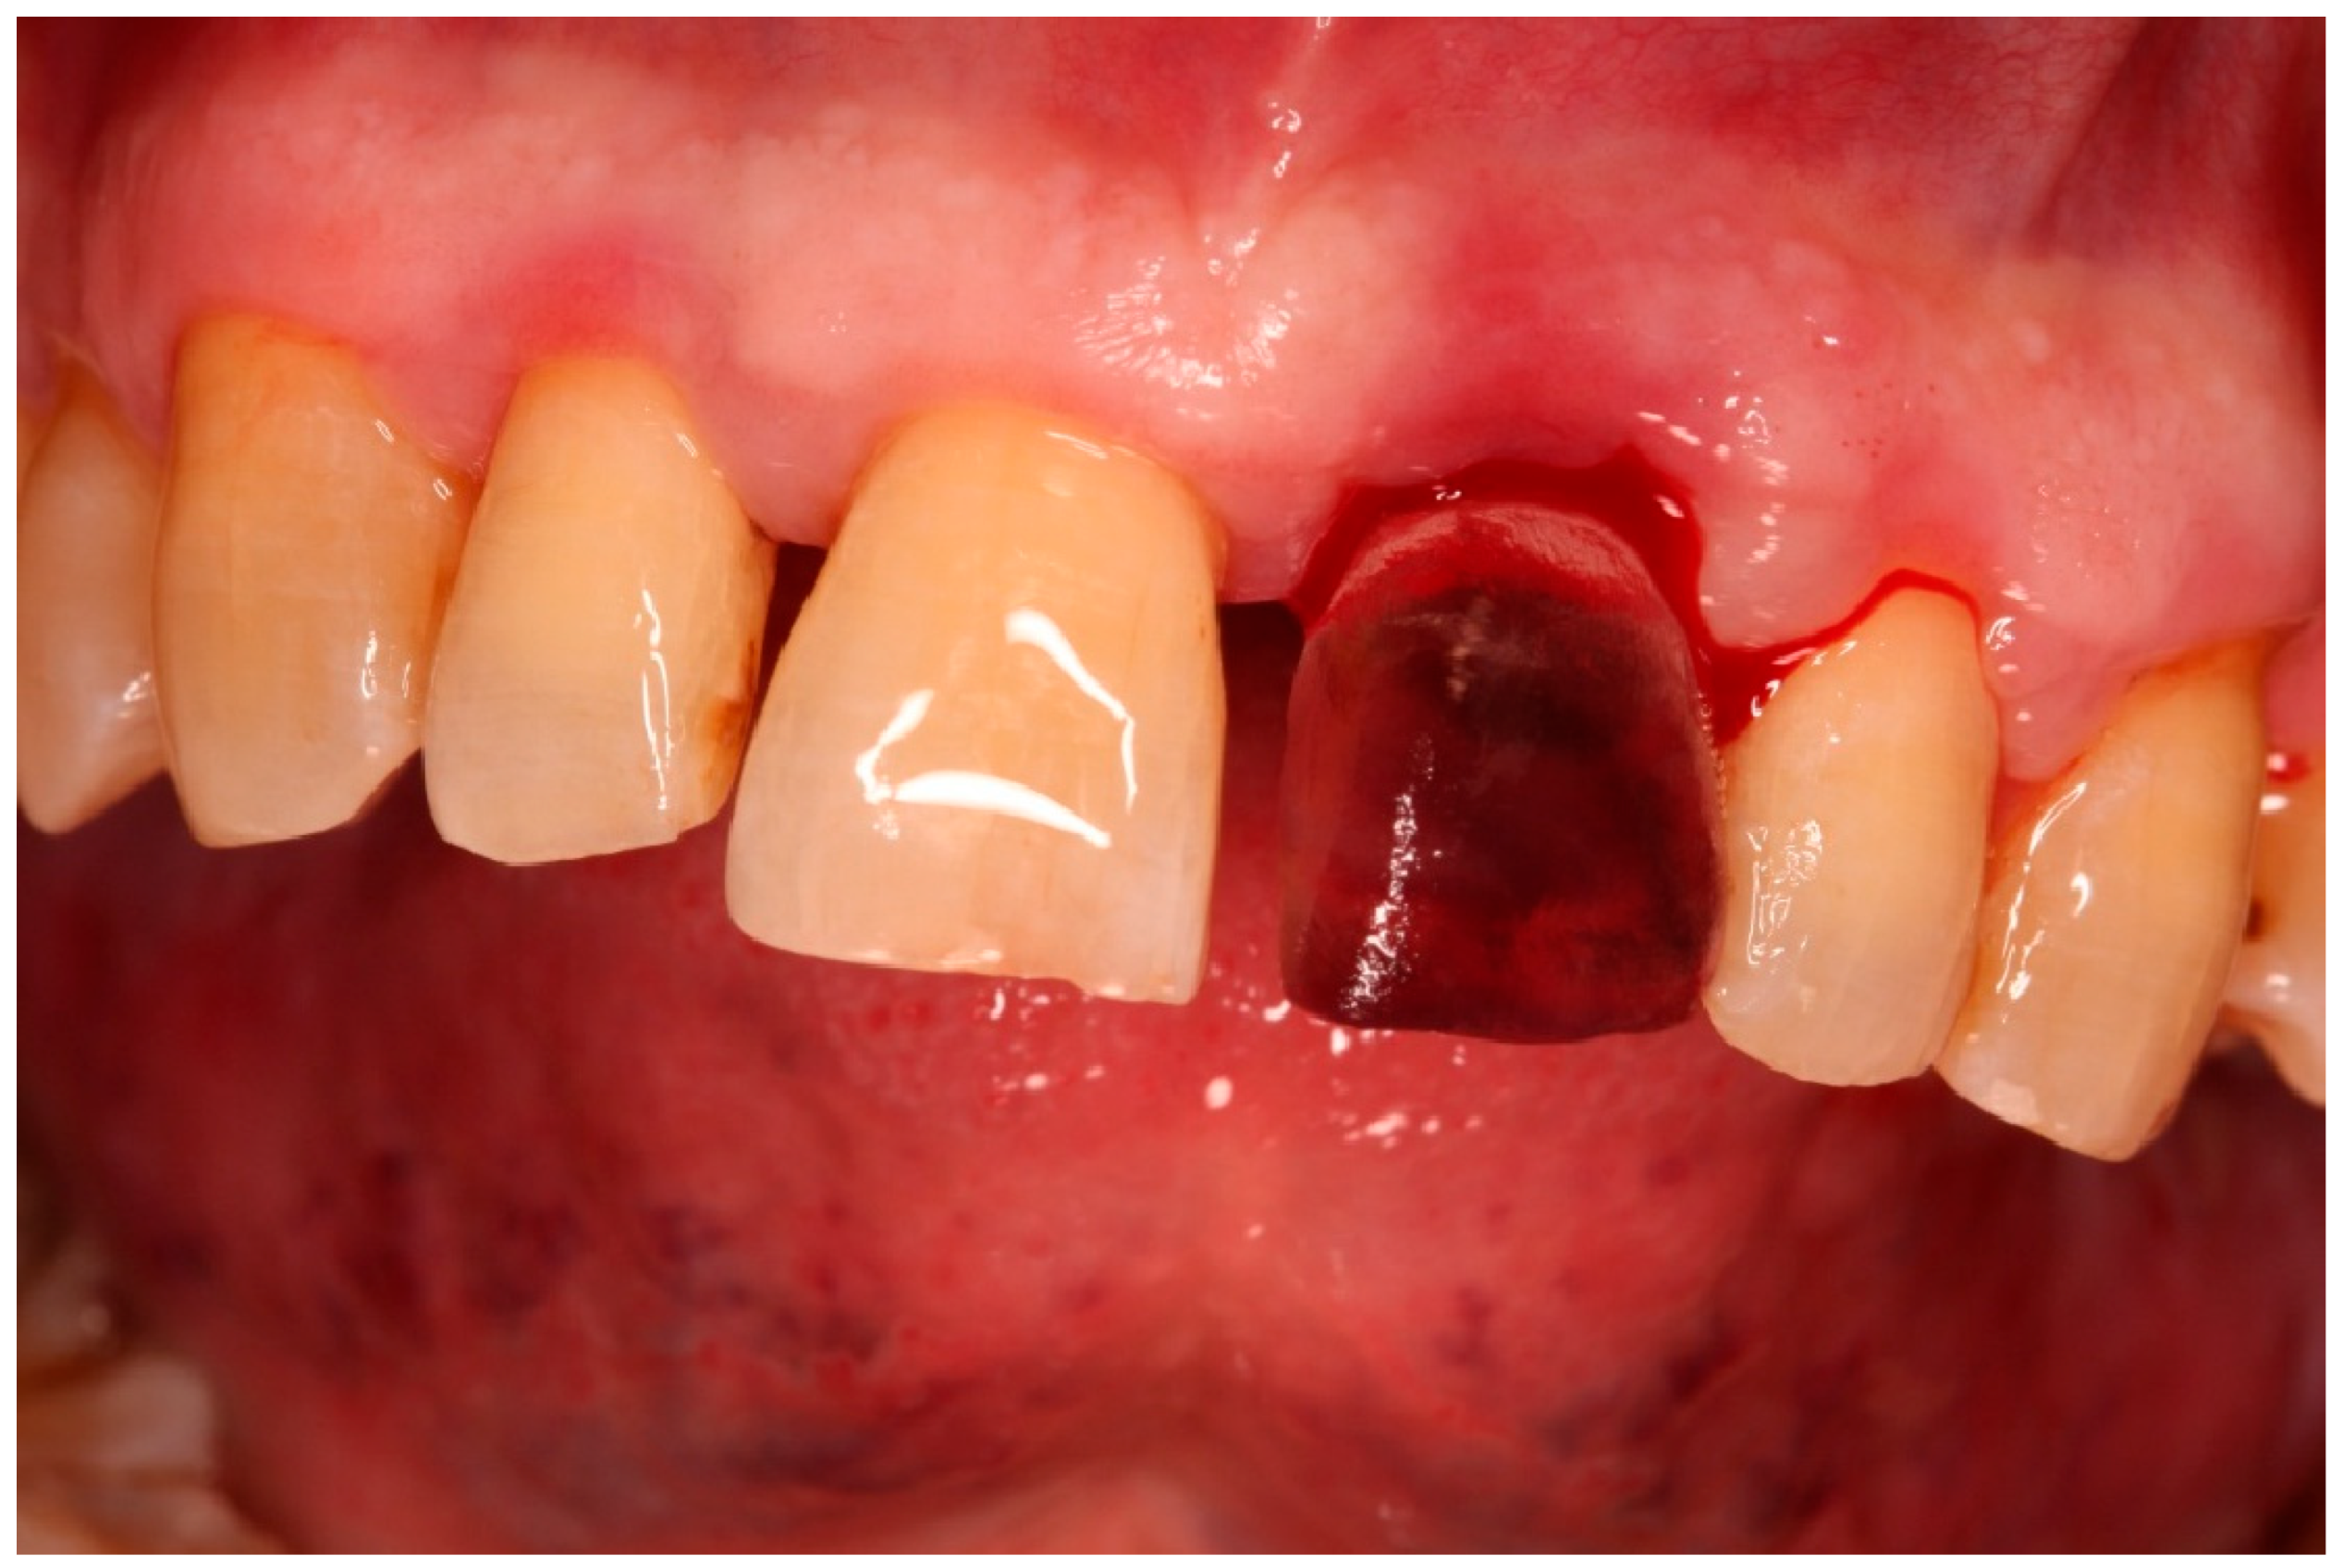

- Atraumatic extraction: Tooth 21 was carefully luxated using periotomes to preserve the PDL and surrounding bone. Immediately after extraction, the tooth was stored in chilled sterile saline (approximately 4–6 °C). The total extraoral period was approximately 10 min.